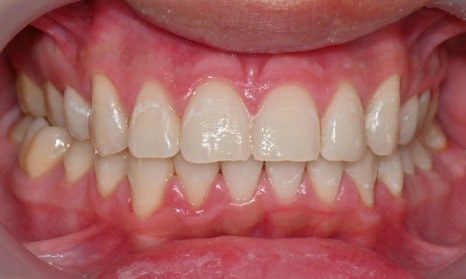

어태치먼트 주변의 착색 및 변색

첫번째 사진은 인비절라인 치료 중인 환자분 사진으로, 어태치먼트 주변으로 착색도 발생한 것을 확인할 수 있습니다. 두번째 사진은 어렸을 때 해외에서 인비절라인을 하다가 어태치먼트를 제거하지 않고 오래 유지를 하다가 내원해서 마무리 교정을 하기 위해 저희 병원에 내원한 환자 사진으로, 어태치먼트 주변이 노랗게 변색된 것을 확인할 수 있습니다.